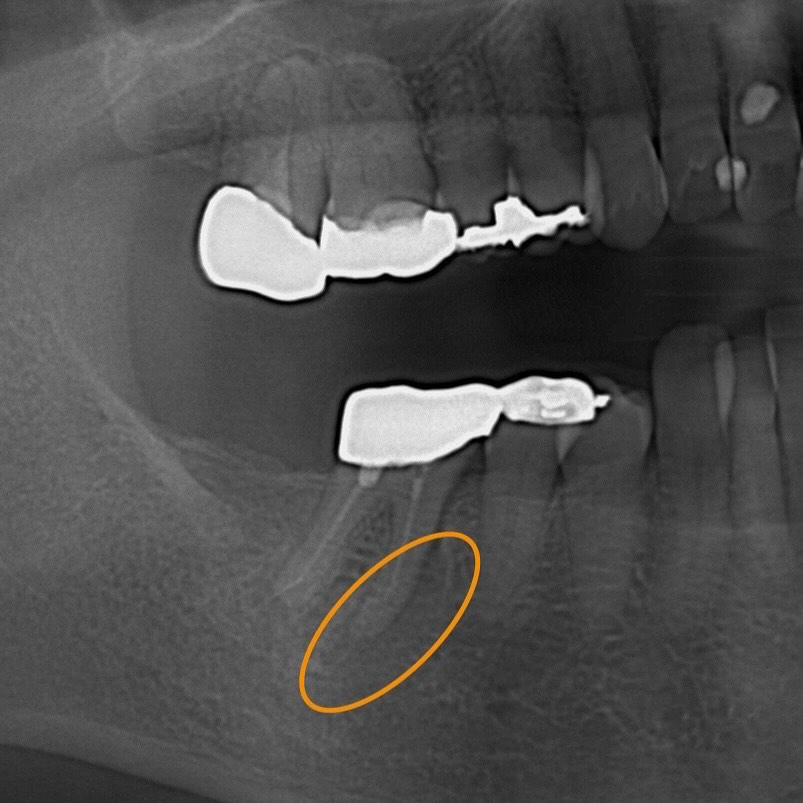

初診時のレントゲンから、治療痕のある歯の歯根先端に膿が溜まっているのが分かります😢